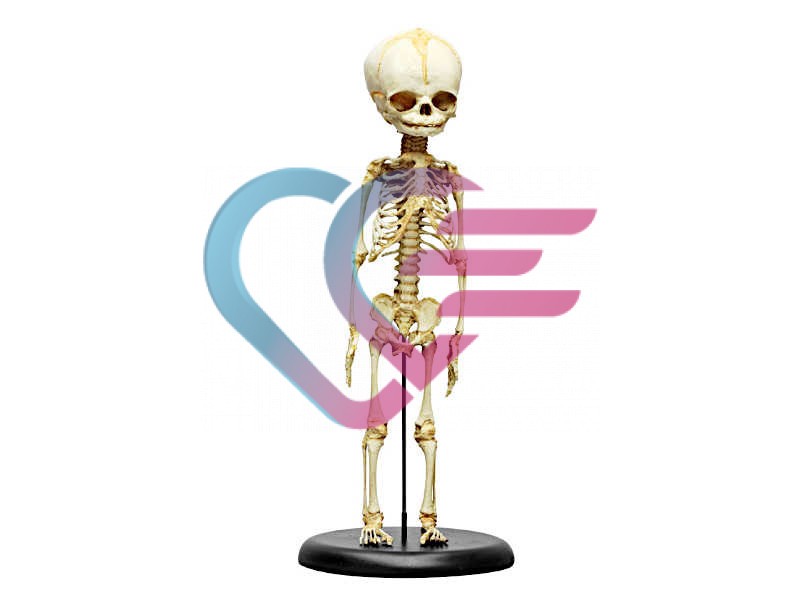

- Prvoklasni odljev kostura djeteta starosti 14 do 16 mjeseci.

- Prikazuje nesrasle epifize dugih kostiju i hrskavične rubove mnogih kostiju što je tipično za ovo doba razvoja.

- Sve fisure i otvori su pažljivo reproducirani.

- Udovi su ograničeno pokretljivi.

- Visina: 65 cm.

- Isporučuje se sa stalkom.

KOSTUR (SKELET) DJETETA STAROSTI 14 DO 16 MJESECI

- Prvoklasni odljev kostura djeteta starosti 14 do 16 mjeseci.

- Prikazuje nesrasle epifize dugih kostiju i hrskavične rubove mnogih kostiju što je tipično za ovo doba razvoja.

- Sve fisure i otvori su pažljivo reproducirani.

- Udovi su ograničeno pokretljivi.

- Visina: 65 cm.

- Isporučuje se sa stalkom.